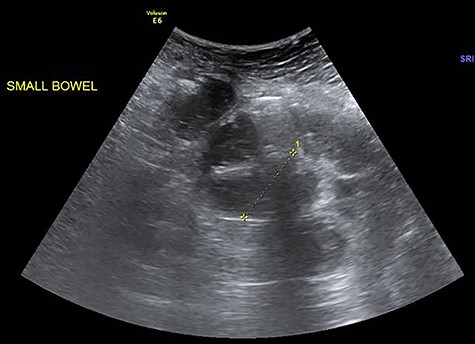

Erect abdominal film demonstrated dilated small bowels alongside the presence of air-fluid filled loops (Fig. 1). Abdominal ultrasound revealed extensively dilated small bowels with multiple gas-filled levels with maximum diameter of 3.5 cm (Fig. 2). Computed tomography (CT) showed the presence of dilated small bowels and local bowel thickening, compatible with the features of small bowel obstruction (Fig. 3). Laboratory data were grossly normal with no evidence of electrolyte abnormalities or increased white blood cell count.

Fluid-filled small bowels with dilatation (widest diameter: 3.5 cm).